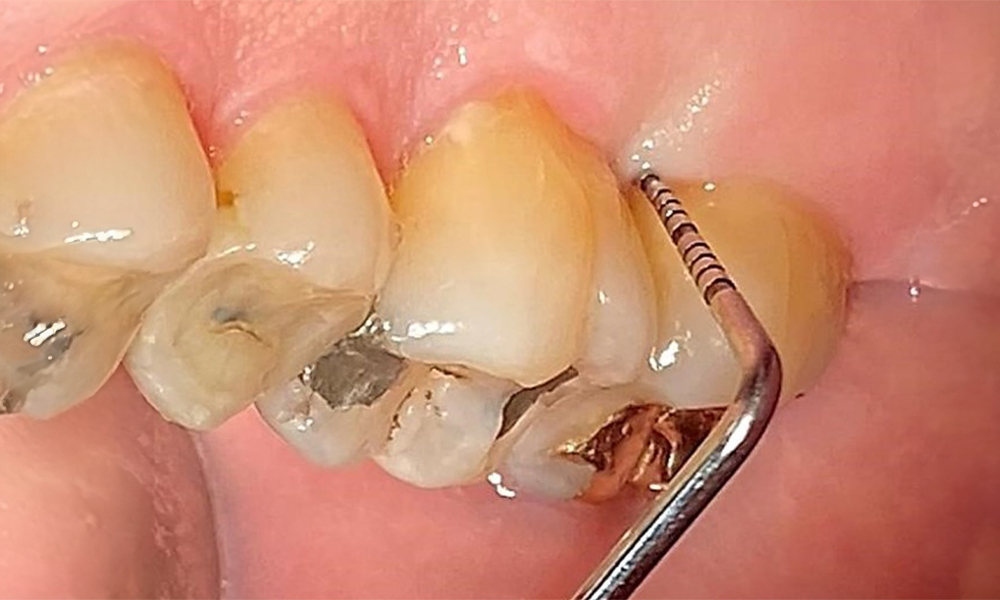

Occlusal view of the maxilla. Insufficient amalgam filling of 14 with a marginal gap.

Fig. 5 Occlusal view of the maxilla. Insufficient amalgam filling of 14 with a marginal gap. © Dr R. Krapf

The patient has a full dentition with 28 teeth, which includes amalgam and composite fillings in the molar and premolar regions. There is a visible clinical marginal gap present on tooth 14. Tooth 27 has an adequate gold inlay. There are also generalized attritions and abrasions. (Fig. 2, Fig. 3, Fig. 4, Fig. 5, Fig. 6)